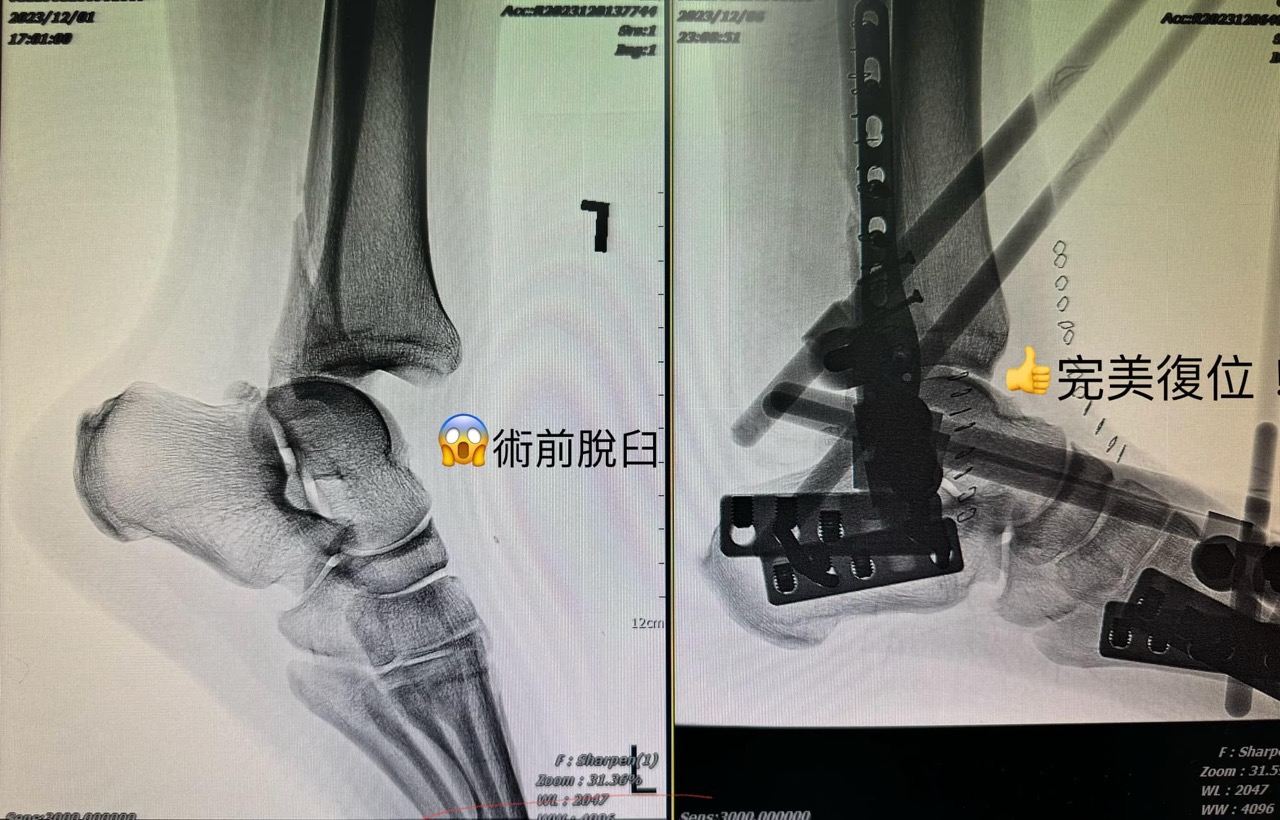

追求99.9%完美!骨科醫師的執念,一台腳踝骨折手術改變患者一生的關鍵

其實我覺得專精於 #脊椎微創手術 的醫師或多或少都有些「偏執狂」,

總覺得還可以做得更好,不逼死自己絕不罷休。